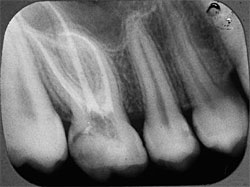

Рентгенологические снимки хорошо запломбированных корневых каналов.